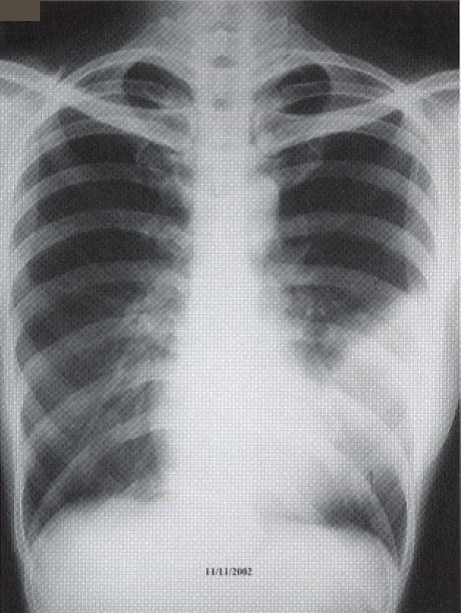

A 41-year old secretary was found having a left mid zone opacity on a routine CXR taken as part of her annual medical check-up (fig. la). This radiographic abnormality persisted after she was given a course of Azithromycin by her family physician (fig. 1b). She was a lifelong non-smoker with a past history of hyperthyroidism treated with drugs for 18 months in 1985-86 and had been euthyroid since. Two months prior to her medical check-up, she had a flu-like illness with cough and a sore throat that lasted for about a fortnight. She had been asymptomatic since apart from a slight cough occasionally. She denied any fever, weight loss, night sweat or pruritus. There was no history of taking any long-term medication or exposure to chemicals or animal pets. Clinical examination was normal and in particular, she was afebrile and not in respiratory distress. SaO2was 98% at rest whilst she was breathing room air and spirometry was normal.

Fig. 1: CXR taken at presentation (a) and 17 days later (b). Left mid zone opacity remained unchanged despite a course of Azithromycin Blood tests revealed normal CBP, ESR & routine biochemistry. Antibodies for HIV 1 & 2 were negative. Thyroid function was normal but thyroid peroxidase antibody was elevated at 81.7 IV/ml (normal <12). CT thorax showed an area of segmental consolidation in the lingular segment of left upper lobe (fig. 2a), with no abnormality detected in other parts of the lungs, mediastinum or body structures. Bronchoscopy revealed nothing abnormal and bronchial washings grew alpha streptococcus but were negative for AFB smear, M tuberculosis DNA or malignant cells. She developed a cough after the bronchoscopy and responded to a course of levofloxacin.

Fig. 1: CXR taken at presentation (a) and 17 days later (b). Left mid zone opacity remained unchanged despite a course of Azithromycin Blood tests revealed normal CBP, ESR & routine biochemistry. Antibodies for HIV 1 & 2 were negative. Thyroid function was normal but thyroid peroxidase antibody was elevated at 81.7 IV/ml (normal <12). CT thorax showed an area of segmental consolidation in the lingular segment of left upper lobe (fig. 2a), with no abnormality detected in other parts of the lungs, mediastinum or body structures. Bronchoscopy revealed nothing abnormal and bronchial washings grew alpha streptococcus but were negative for AFB smear, M tuberculosis DNA or malignant cells. She developed a cough after the bronchoscopy and responded to a course of levofloxacin.

The radiographic changes of pulmonary MALToma are non-specific. CXR and High resolution CT thorax usually show multi-focal, ill-defined nodules containing air bronchograms or focal lobar consolidation similar to what is seen in this patient. Mediastinal lymphadenopathy and pleural changes are rare. These features are similar to those seen in bronchoalveolar cell carcinoma or bronchiolitis obliterans with organizing pneumonia (3). The possibility of MALToma should be considered in patients with non-resolving pneumonia, especially if there is an absence of prominent systemic or respiratory symptoms.